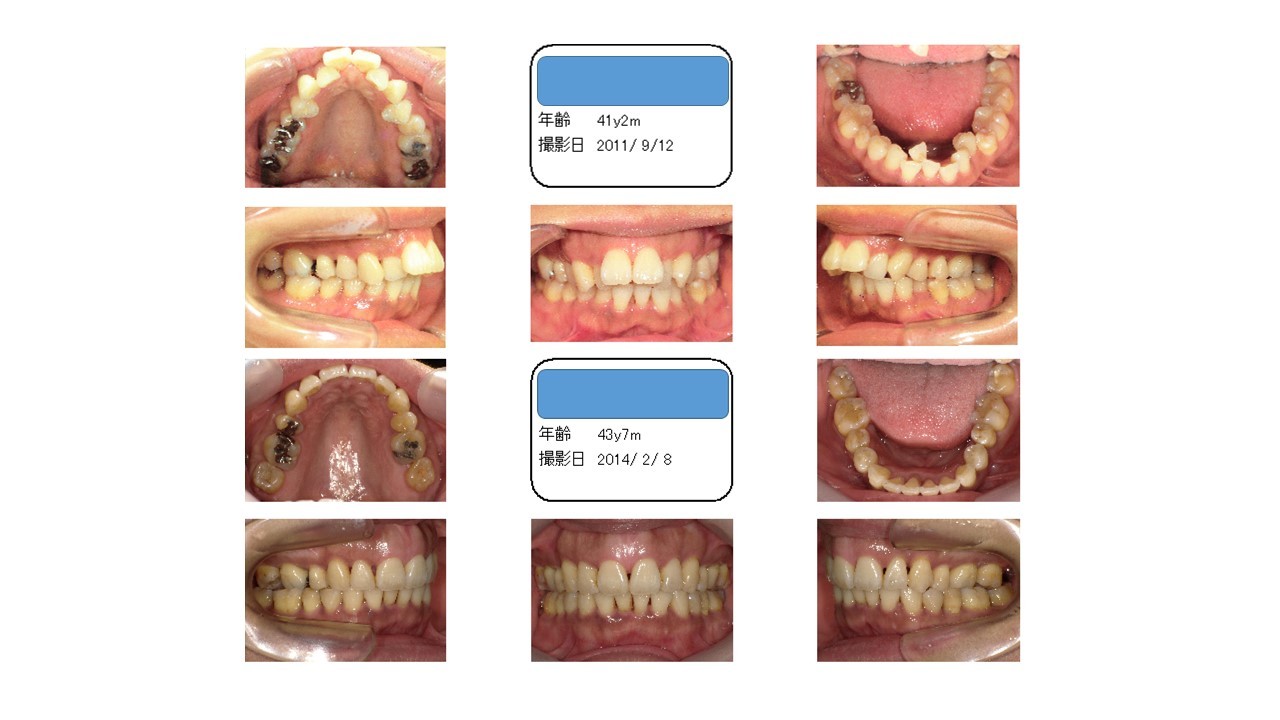

デコボコ・出っ歯 40代

最初上の前歯が下の前歯に対して出ている、いわゆる出っ歯という歯並びでした。

上が出ているのを下げるには、隙間を作らなくてはいけません。そのために、上の歯を2本抜かせてもらっています。

一方で、下の歯列にも大きなデコボコがあります。デコボコがあるのは、隙間が足りていないからなので、隙間を作らないといけません。

そのために、歯を抜くという選択をすることがあるのですが、このケースの場合、それはできません。

なぜかというと、下の歯も抜いてしまうと、下の前歯も下がってしまうので、出っ歯が治らなくなるからです。

ですので、歯が入るだけの隙間を拡げて並べています。

そこに少し治療期間を頂きました。

でもスゴくキレイになったと思います。

左右上一本ずつ歯を抜いて隙間を作り、上の前歯を後ろに下げます。ブラケット装置にて治療。